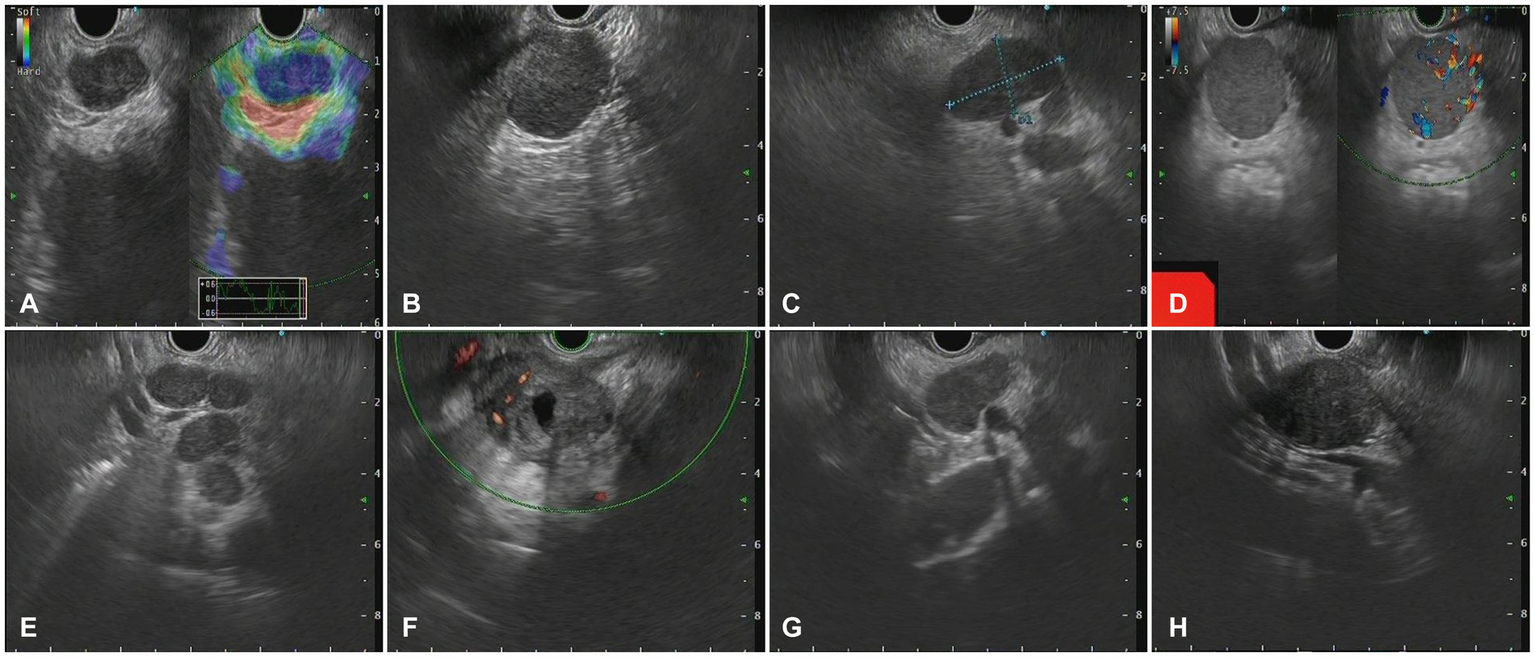

Figure 4

The Endoscopic ultrasonography image features in patients with metastatic tumors. (A) A case of cholangiocarcinoma. EUS showed multiple hypoechoic mass shadows, Doppler showed no blood flow signal, and the texture of elastic imaging was hard. (B) A case of gallbladder carcinoma. EUS showed low echo fusion lymph node shadow (C) A case of lung cancer. EUS showed multiple uniform hypoechoic nodules, some of which were fused with unclear boundaries, Doppler imaging showed no obvious blood flow signal, and the texture of elastic imaging was hard. (D) A case of liver cancer. EUS showed a class of circular lesions with uniform hypoechoic changes and Doppler blood flow signals. (E) A case of colon cancer. EUS showed multiple hypoechoic nodules, some of which were fused into clusters, with clear boundaries and homogeneous internal echoes. (F) A case of gastric cancer. EUS showed multiple hypoechoic nodules, which were round, with clear boundaries, anechoic, and non-uniform echoic necrosis. (G) A case of thymic carcinoma. EUS showed multiple enlarged lymph nodes with clear boundaries, and no obvious blood flow signal was observed by Doppler. (H) A case of rectal cancer. EUS scan showed circular hypoechoic lesions with partial fusion, and the Doppler scan showed no obvious blood flow signal.